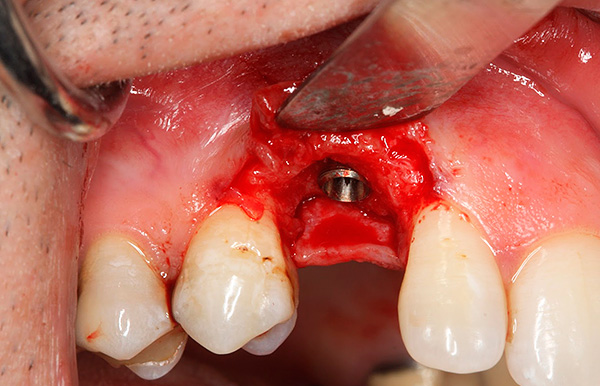

As fotos abaixo mostram os implantes removidos:

Após a remoção do implante móvel, é realizada uma preparação complexa do poço para a próxima implantação, que pode ser realizada após 1-2 meses. Por exemplo, com uma diminuição significativa no tecido ósseo ou na proximidade do seio maxilar, pode ser necessário construir o osso da mandíbula sob o implante dentário (operação de elevação do seio).